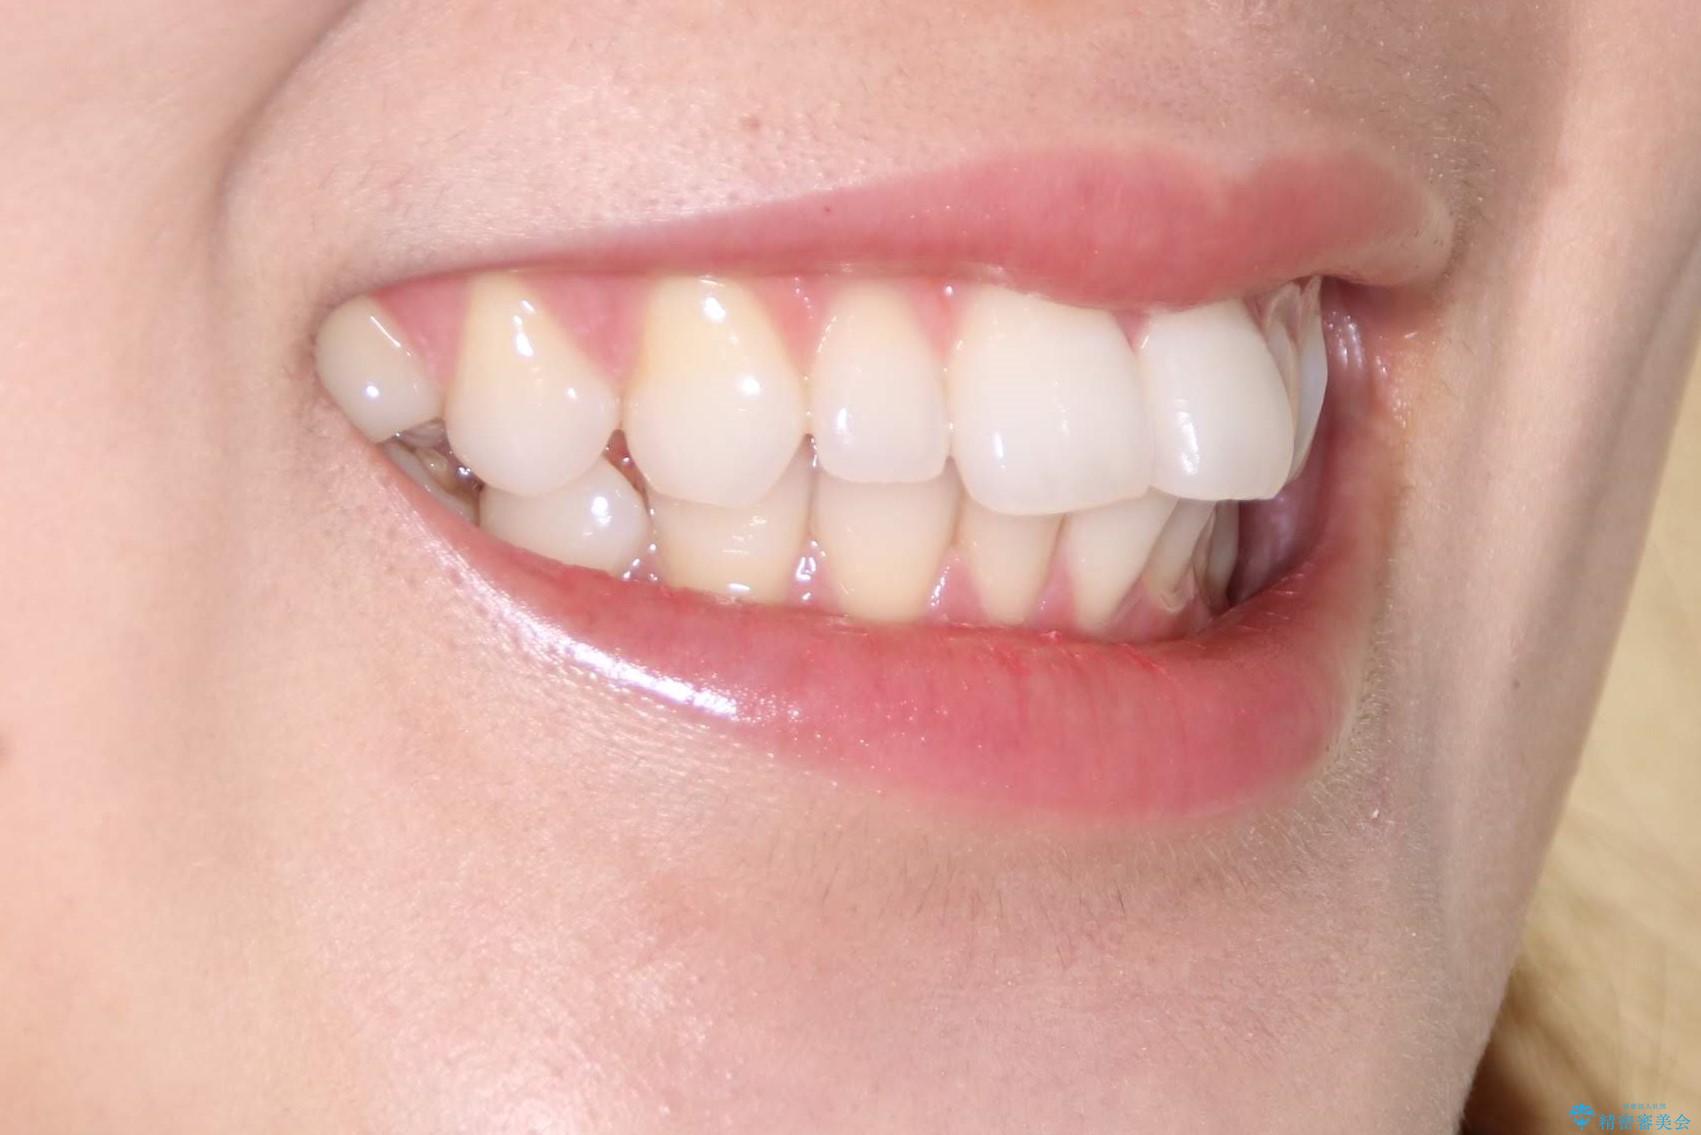

インビザラインで出っ歯を改善する 抜歯をしないinvisalign治療

- 20代女性

- 1年5ヶ月

- 非抜歯・遠心移動による前突の改善をマウスピースにて計画した。

非抜歯矯正の場合、大きく前歯を下げることはできませんが、奥歯の遠心移動や歯のサイズダウンにより歯軸を立て、見かけ上の出っ歯感をある程度改善することができます。